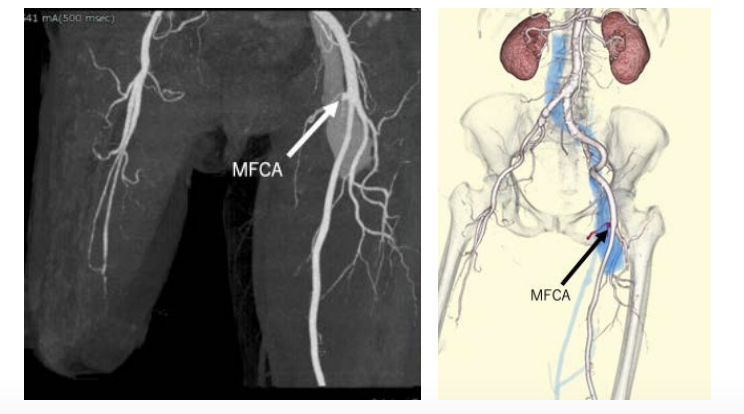

This patient was a 67-year-old woman who had been caught in a cultivator and had her right leg amputated in the 1980s. She had no medical history of congestive heart failure or shortness of breath. She was administered direct oral coagulant, a β-blocker, and a proton pump inhibitor because of chronic atrial fibrillation. Twenty-seven years after the accident, she presented to our hospital because of a swollen left leg and shortness of breath. Her blood pressure was 125/82 mmHg, heart rate was 100/min with atrial fibrillation, and saturation was 95% in room air. The results of a complete blood test as well as renal, liver, and thyroid function tests were all normal but the serum BNP level rose to 607.1 pg/mL. Chest radiography confirmed cardiac dilation, pulmonary congestion, and pleural effusion (Figure 1). She was given 20 mg/day furosemide to treat congestive heart failure. We confirmed a bruit at her left groin and pulsations in a lower leg vein. Transthoracic echo cardiography (TTE) showed an ejection fraction of 55%, her right ventricular pressure increased to 44 mmHg, and severe tricuspid valve regurgitation was detected. Vascular echo showed an arteriovenous fistula (AVF), shunt flow, and an expanded femoral vein (Figure 2). A computed tomography (CT) angiography was performed and revealed a left medial femoral circumflex artery (MFCA)–left common femoral vein (CFV) fistula (Figure 3).

Although the MFCA usually arises from the deep femoral artery,9 in the present patient it arose directly from the common femoral artery (CFA) directly. Tomaszewski et al reported that 64.6% of MFCAs originated from the DFA whereas 32.2% of them originated from the CFA.10 Although an iatrogenic MFCA–CFV fistula caused by FV canulation was recently reported,11 an MFCA–CFV fistula formed by trauma has not been reported to date. CT angiography and vascular sonography can be very useful in the diagnosis of AVF and in the development of a treatment strategy.